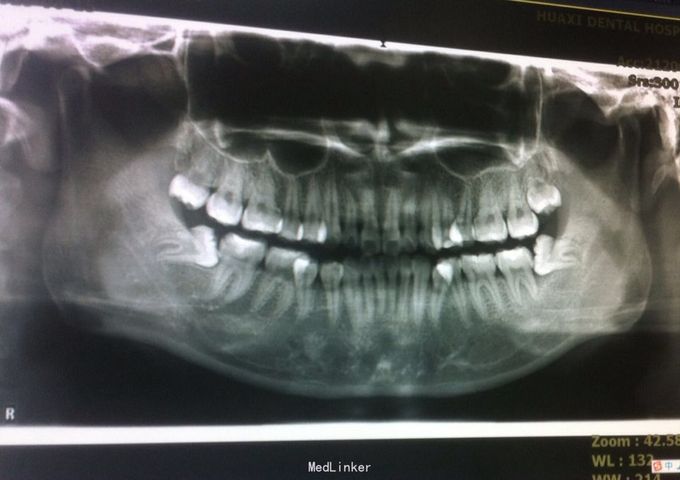

恒牙期 左侧磨牙中性关系,右侧远中关系 前牙三度深覆合 上合牙列中度拥挤,下颌重度拥挤 下颌中线偏右 关节有弹响

安氏二类,牙列拥挤 拔牙矫治,拔除14、24、34、44,强支抗,排齐整平上下牙列,矫治后磨牙中性关系,前牙覆合覆盖正常,面型略改善

1、治疗中可能需植入微种植体内收前牙 2、18、28、38、48存在,必要时建议拔除 3、正畸治疗后面型可能仍略突